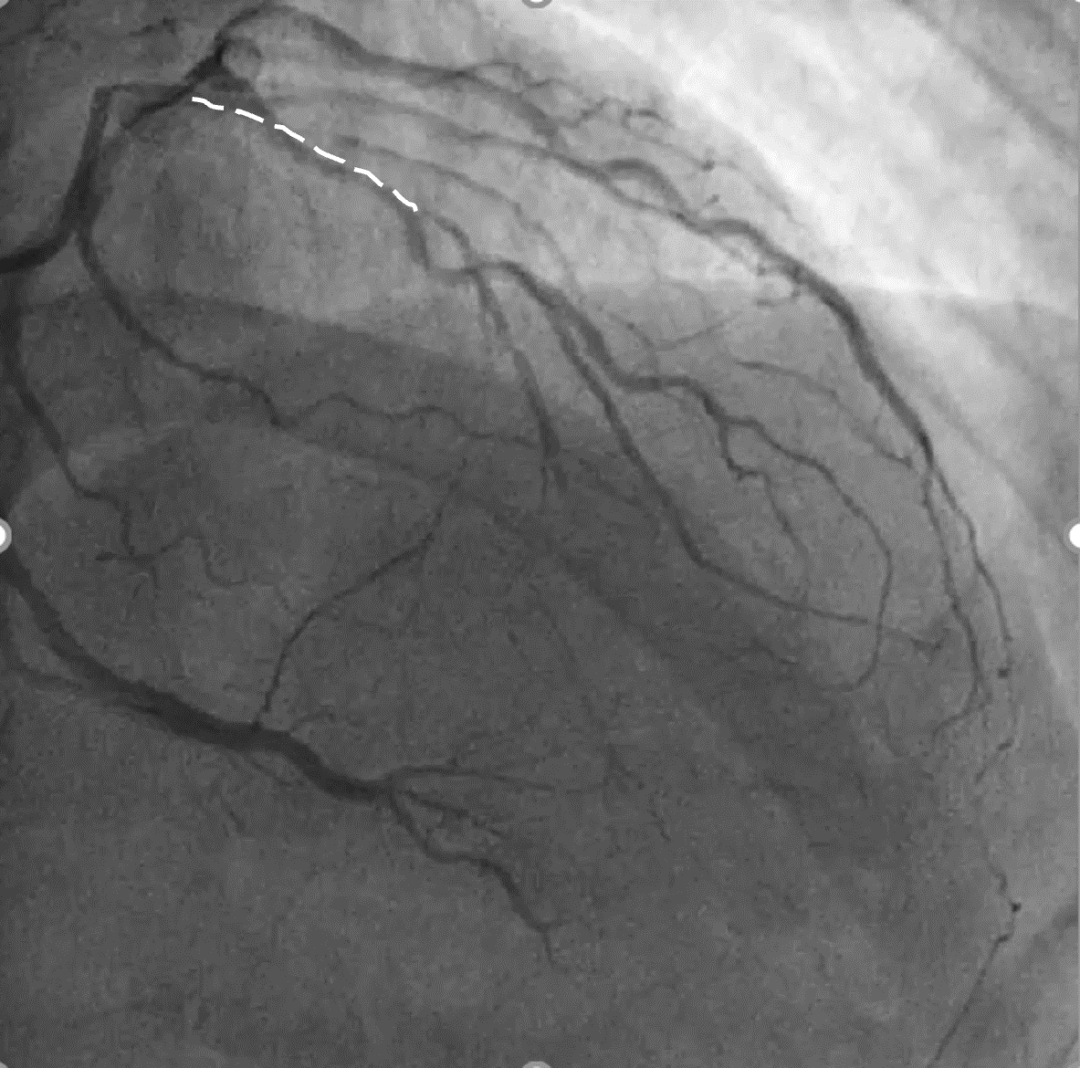

手术影像

LAD、LCX双支 CTO ,LAD 近端50%狭窄

RCA粗大,支架代偿良好。远端60%狭窄,PDA开口80%狭窄

策略讨论:双支CTO,闭塞段残端清晰,钙化,右冠造影可见PLV/PDA侧供LCA。由于有前降支PCI失败史,该次已经做好充分准备,大概率需要逆向PCI。